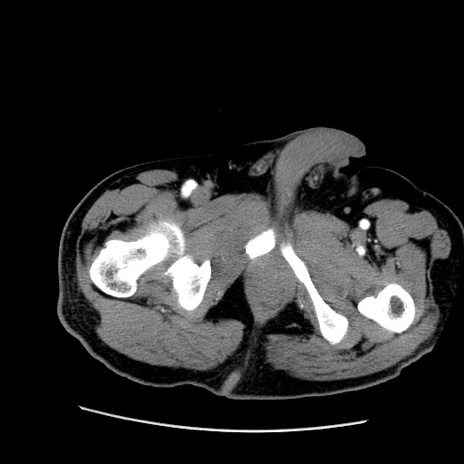

症例22(横断像)

【症例】50歳代男性

【主訴】腹痛

【現病歴】AVMからの被殻出血のため回復期リハ病棟入院中。 本日午後3時頃急に下腹部痛が出現した。

【既往歴】AVM、被殻出血、虫垂炎、高血圧

【身体所見】意識晴明、左半身不全麻痺、会話の理解は良好、36.5°C、腹部:膨隆、全体に板状硬、下腹部正中に圧痛点あり、反跳痛-、筋性防御不明、右下腹部にope scar

【データ】WBC 9400、CRP 0.06